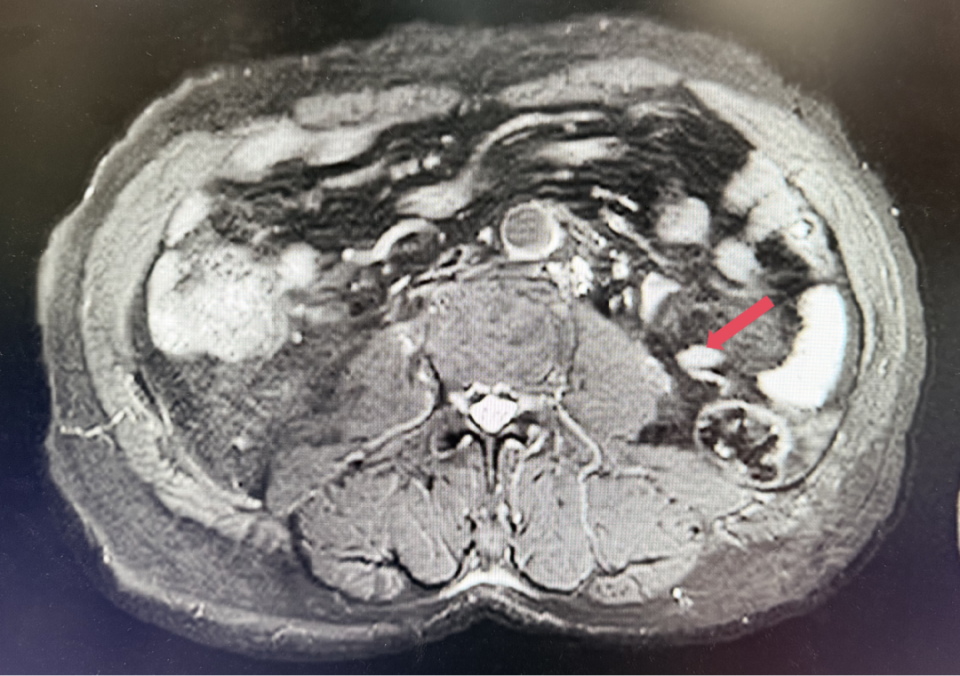

2023年1月,基线

2022年3月:患者因“左腰痛”复查。胸部CT提示双肺微小结节,较前未见明显变化;腹盆MR示:左侧腹膜后多发结节及肿块影,较大者约5.7cm*5.1cm;考虑患者诊断为转移性肾透明细胞癌,IV期,IMDC评分0分,低危组。予培唑帕尼一线治疗8个月,最佳疗效SD。

2023年1月开始使用呋喹替尼联合信迪利单抗方案,具体方案为:呋喹替尼5mg,po,qd,D1-14+信迪利单抗200mg,ivgtt,D1,q3w。患者基线肿瘤负荷为128.5mm。